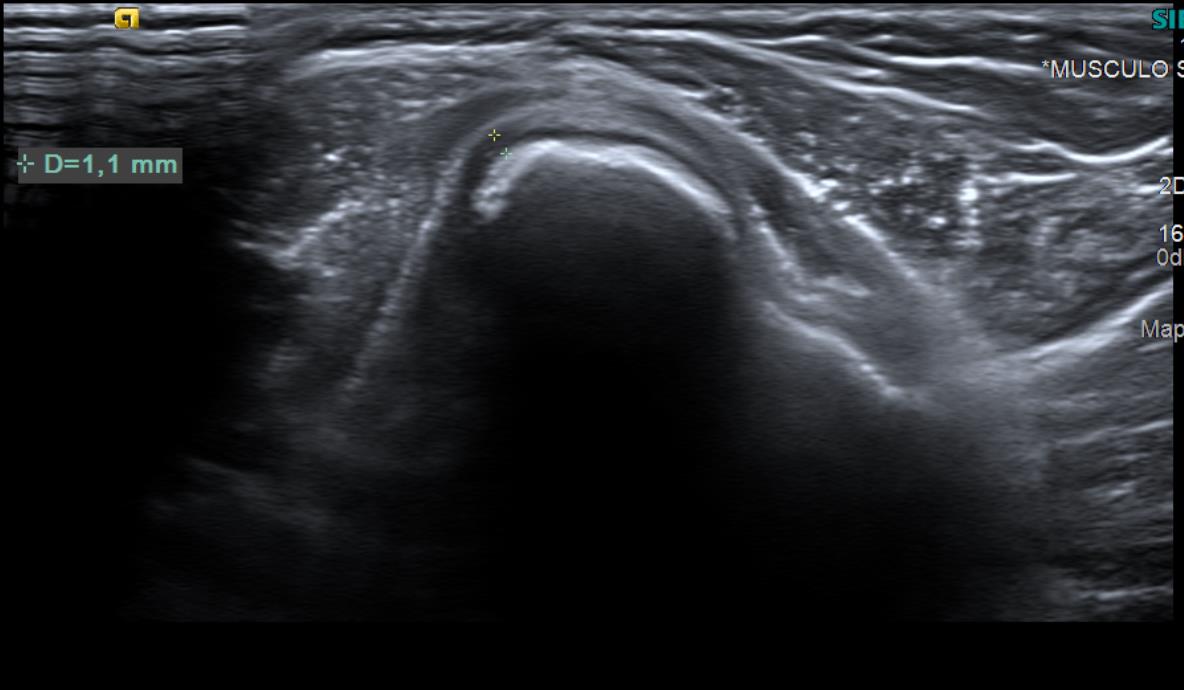

Con el objetivo de no irradiar al escolar, se decide realizar una ecografía desde el centro de salud, para poder obtener una mayor aproximación diagnóstica.

Ecografía: La tumoración referida corresponde a una excrecencia ósea con ribete hipoecoico circunante de 1 mm de espesor, sugestiva de lesión osteocondral.

Tras visualizar alteración en la ecografía del centro de salud, se deriva a radiología para realizar ecografía reglada y completar estudio con radiografía, así como realizar derivación para valoración por parte de Traumatología del Hospital Santa Lucía.